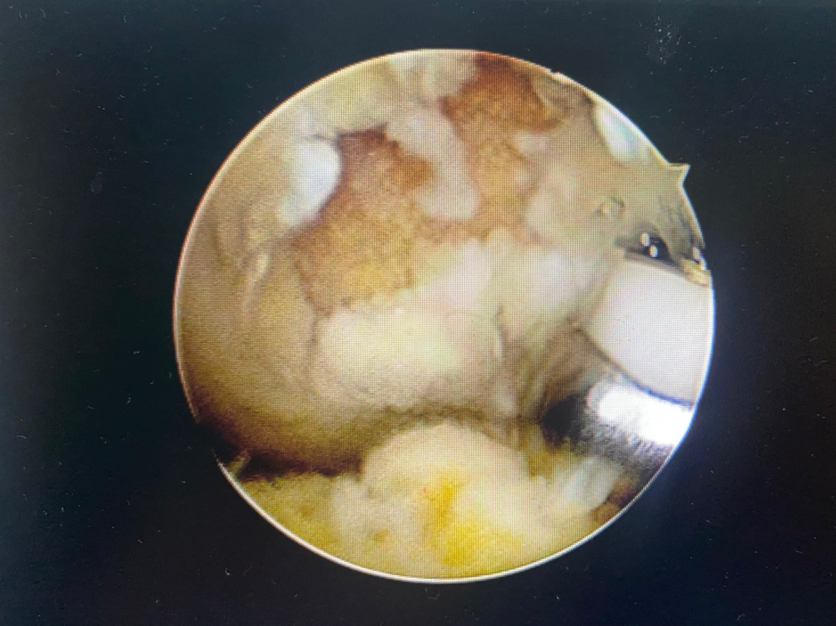

1展示关节镜微创技术:凝胶修复软骨损伤(髌骨软骨损伤凝胶支架修复)

2 膝关节股骨滑车软骨损伤凝胶支架修复

清理微骨折处理

微骨折后骨髓骨细胞溢出

注射凝胶支架覆盖软骨损伤区

软骨修复后(完全覆盖填充)